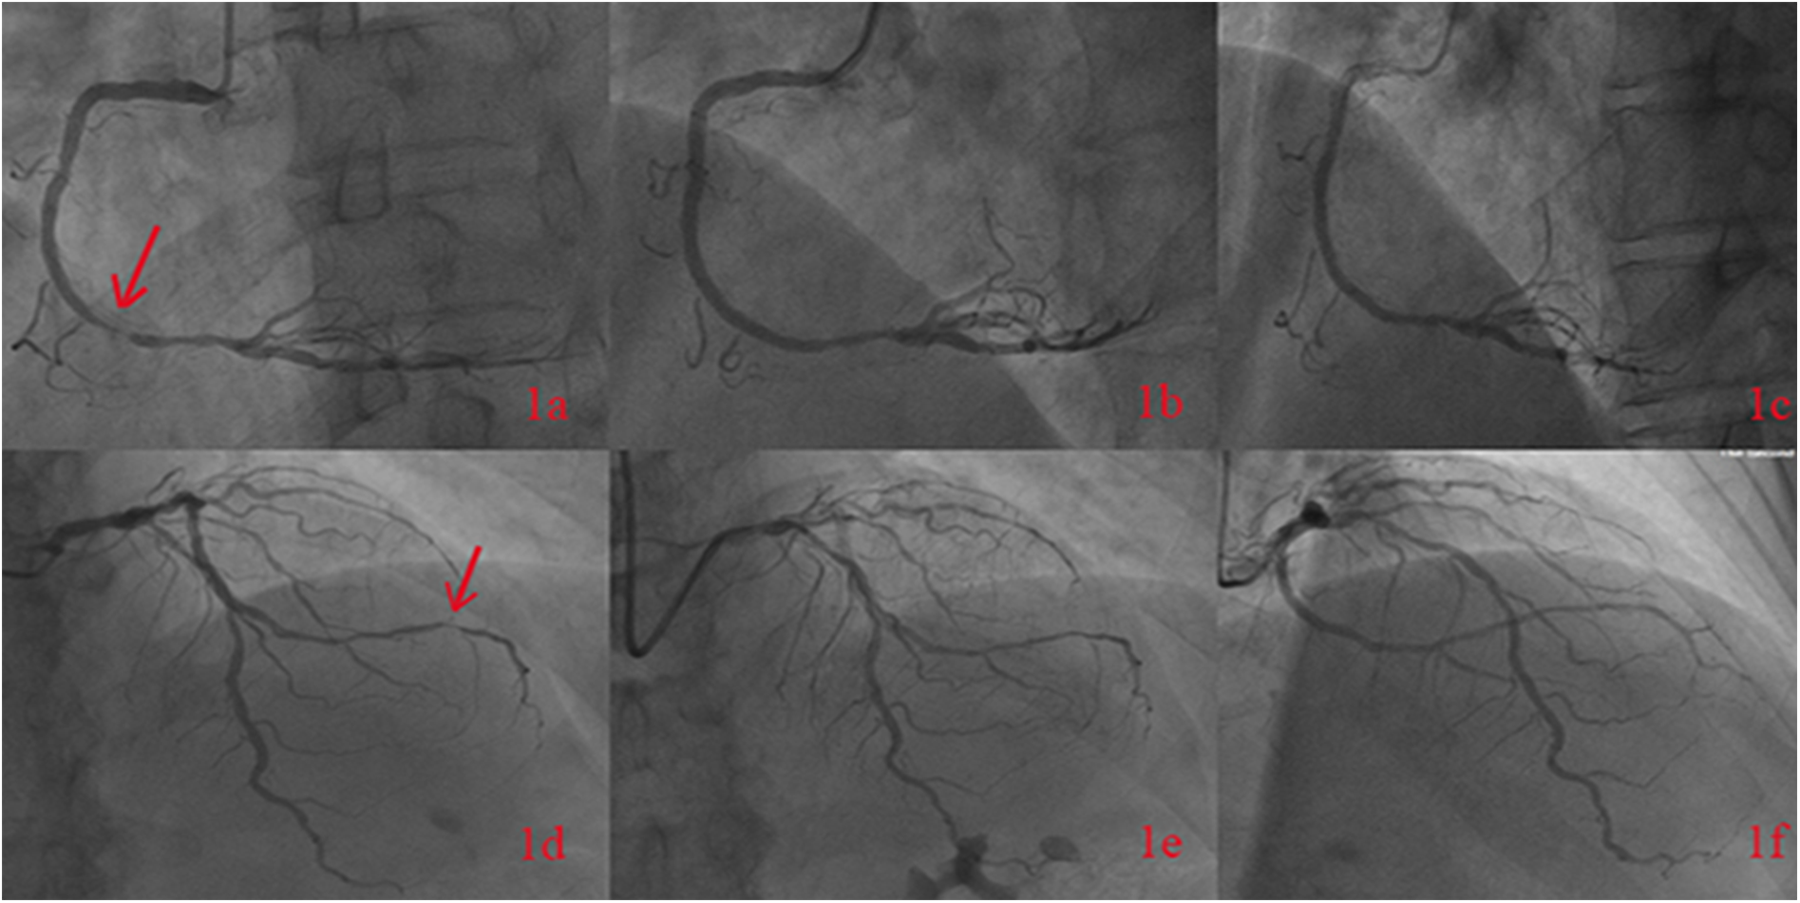

A 65-year-old male was admitted to the Department of Cardiology at the Second Affiliated Hospital of Soochow University on 22 November 2023, with a 13-year history of chest tightness and pain, which had worsened in the past month. Thirteen years prior, he was diagnosed with early-onset CAD and underwent coronary angiography at Lianshui County People's Hospital. The procedure revealed significant stenosis requiring PCI with stent implantation in both the right coronary artery (RCA) and left circumflex artery (LCX). He was prescribed aspirin enteric-coated tablets (100 mg), clopidogrel (75 mg), and pitavastatin calcium (2 mg). Three years ago, the patient presented with chest pain at Zhongda Hospital Southeast University. Follow-up coronary angiography revealed plaque infiltration in the RCA, with a long proximal lesion (90% stenosis) and total occlusion in the mid-segment. Two additional drug-eluting stents were implanted in the RCA. Angiography also identified 30% stenosis in the distal left main artery, 70% stenosis with calcification in the proximal and mid-left anterior descending artery (LAD), and 60% stenosis in the mid-left circumflex artery (LCX), and 75% stenosis in the distal LCX. After discharge, the patient continued aspirin (100 mg), clopidogrel (75 mg), and pitavastatin calcium (2 mg). One month ago, the patient experienced recurrent chest pain. Coronary angiography showed diffuse in-stent proliferation in the proximal and mid-RCA and chronic total occlusion in the LCX stent. Balloon angioplasty was performed following recanalisation. Post-discharge, the patient's therapy was adjusted to aspirin (100 mg), clopidogrel (75 mg), rosuvastatin (10 mg), and ezetimibe (10 mg). However, LDL-C levels remained elevated, and chest pain recurred. Upon admission, the patient's symptoms worsened, including chest pain at rest and profuse sweating. The patient was diagnosed with unstable angina. Laboratory tests indicated total cholesterol of 5.72 mmol/L, triglycerides of 1.78 mmol/L, LDL-C of 4.22 mmol/L, and a clopidogrel genotype of CYP2C19 *1/*2. Electrocardiogram findings revealed T-wave inversion in leads I, avL, V5, and V6. Coronary angiography showed 99% stenosis in the distal RCA stent (Figure 1a), 40% stenosis in the distal left main coronary artery, a 50%–70% stenotic lesion in the proximal and mid-LAD, and 95% stenosis in the distal LCX stent (Figure 1d). Balloon angioplasty was performed on the RCA and distal LCX stents, achieving patent RCA stent with residual stenosis <10% in the distal LCX and thrombolysis in myocardial infarction grade 3 flow (Figures 1b,e). Following the procedure, the patient did not experience chest pain. The patient's therapy was adjusted to rosuvastatin (10 mg), ezetimibe (10 mg), and alirocumab (150 mg biweekly), alongside aspirin (100 mg) and clopidogrel (150 mg). The patient exhibited xanthelasma (Figure 2), refractory hyperlipidaemia, recurrent ISR, and a family history of hyperlipidaemia. Whole exome sequencing revealed a heterozygous LDL receptor (LDLR) gene mutation (c.428G>A, p.Cys143Tyr), consistent with FH. Clinical features and atherosclerotic CVD risk stratification placed the patient in the very high-risk category, warranting LDL-C reduction to <1.4 mmol/L, with a >50% baseline reduction per the European Society of Cardiology guidelines (2). Post-discharge, the patient experienced no chest pain, and LDL-C levels remained at target (Figure 3). One year later, follow-up coronary angiography revealed no progression of RCA lesions (Figure 1c). The left main artery showed approximately 40% stenosis, and LAD stenosis persisted at 50%–70%. The LCX demonstrated mild in-stent neointimal hyperplasia without progression (Figure 1f). The patient remained asymptomatic, and no further ISR occurred. The patient's clinical course is shown in the table below (Table 1).

Figure 1

The figure shows the patient's coronary angiography in November 2023, indicating 99% stenosis in the distal segment of the right coronary artery with a stent (a). Post-balloon angioplasty angiography of the right coronary artery was performed (b), and follow-up angiography in October 2024 revealed no progression of RCA lesions (c). The coronary angiography in November 2023 showed a 95% stenosis in the distal segment of the left circumflex artery (d). Post-balloon angioplasty angiography was performed (e), and follow-up angiography in October 2024 showed the LCX demonstrated mild in-stent neointimal hyperplasia without progression (f).